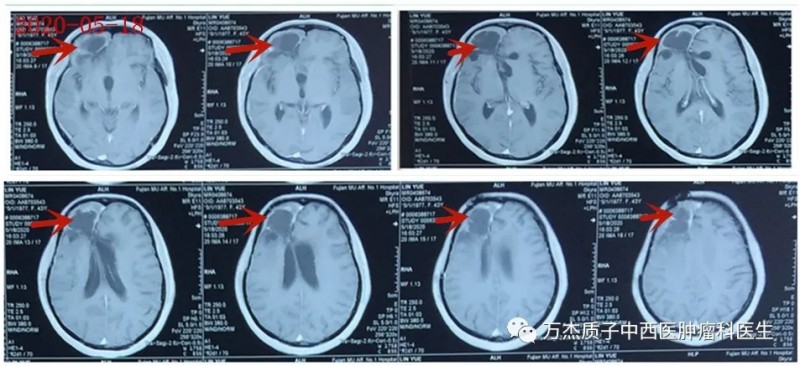

2020-05-18治疗后8月复查MR:病情稳定

2020-11-19治疗后13月复查MR:病情稳定